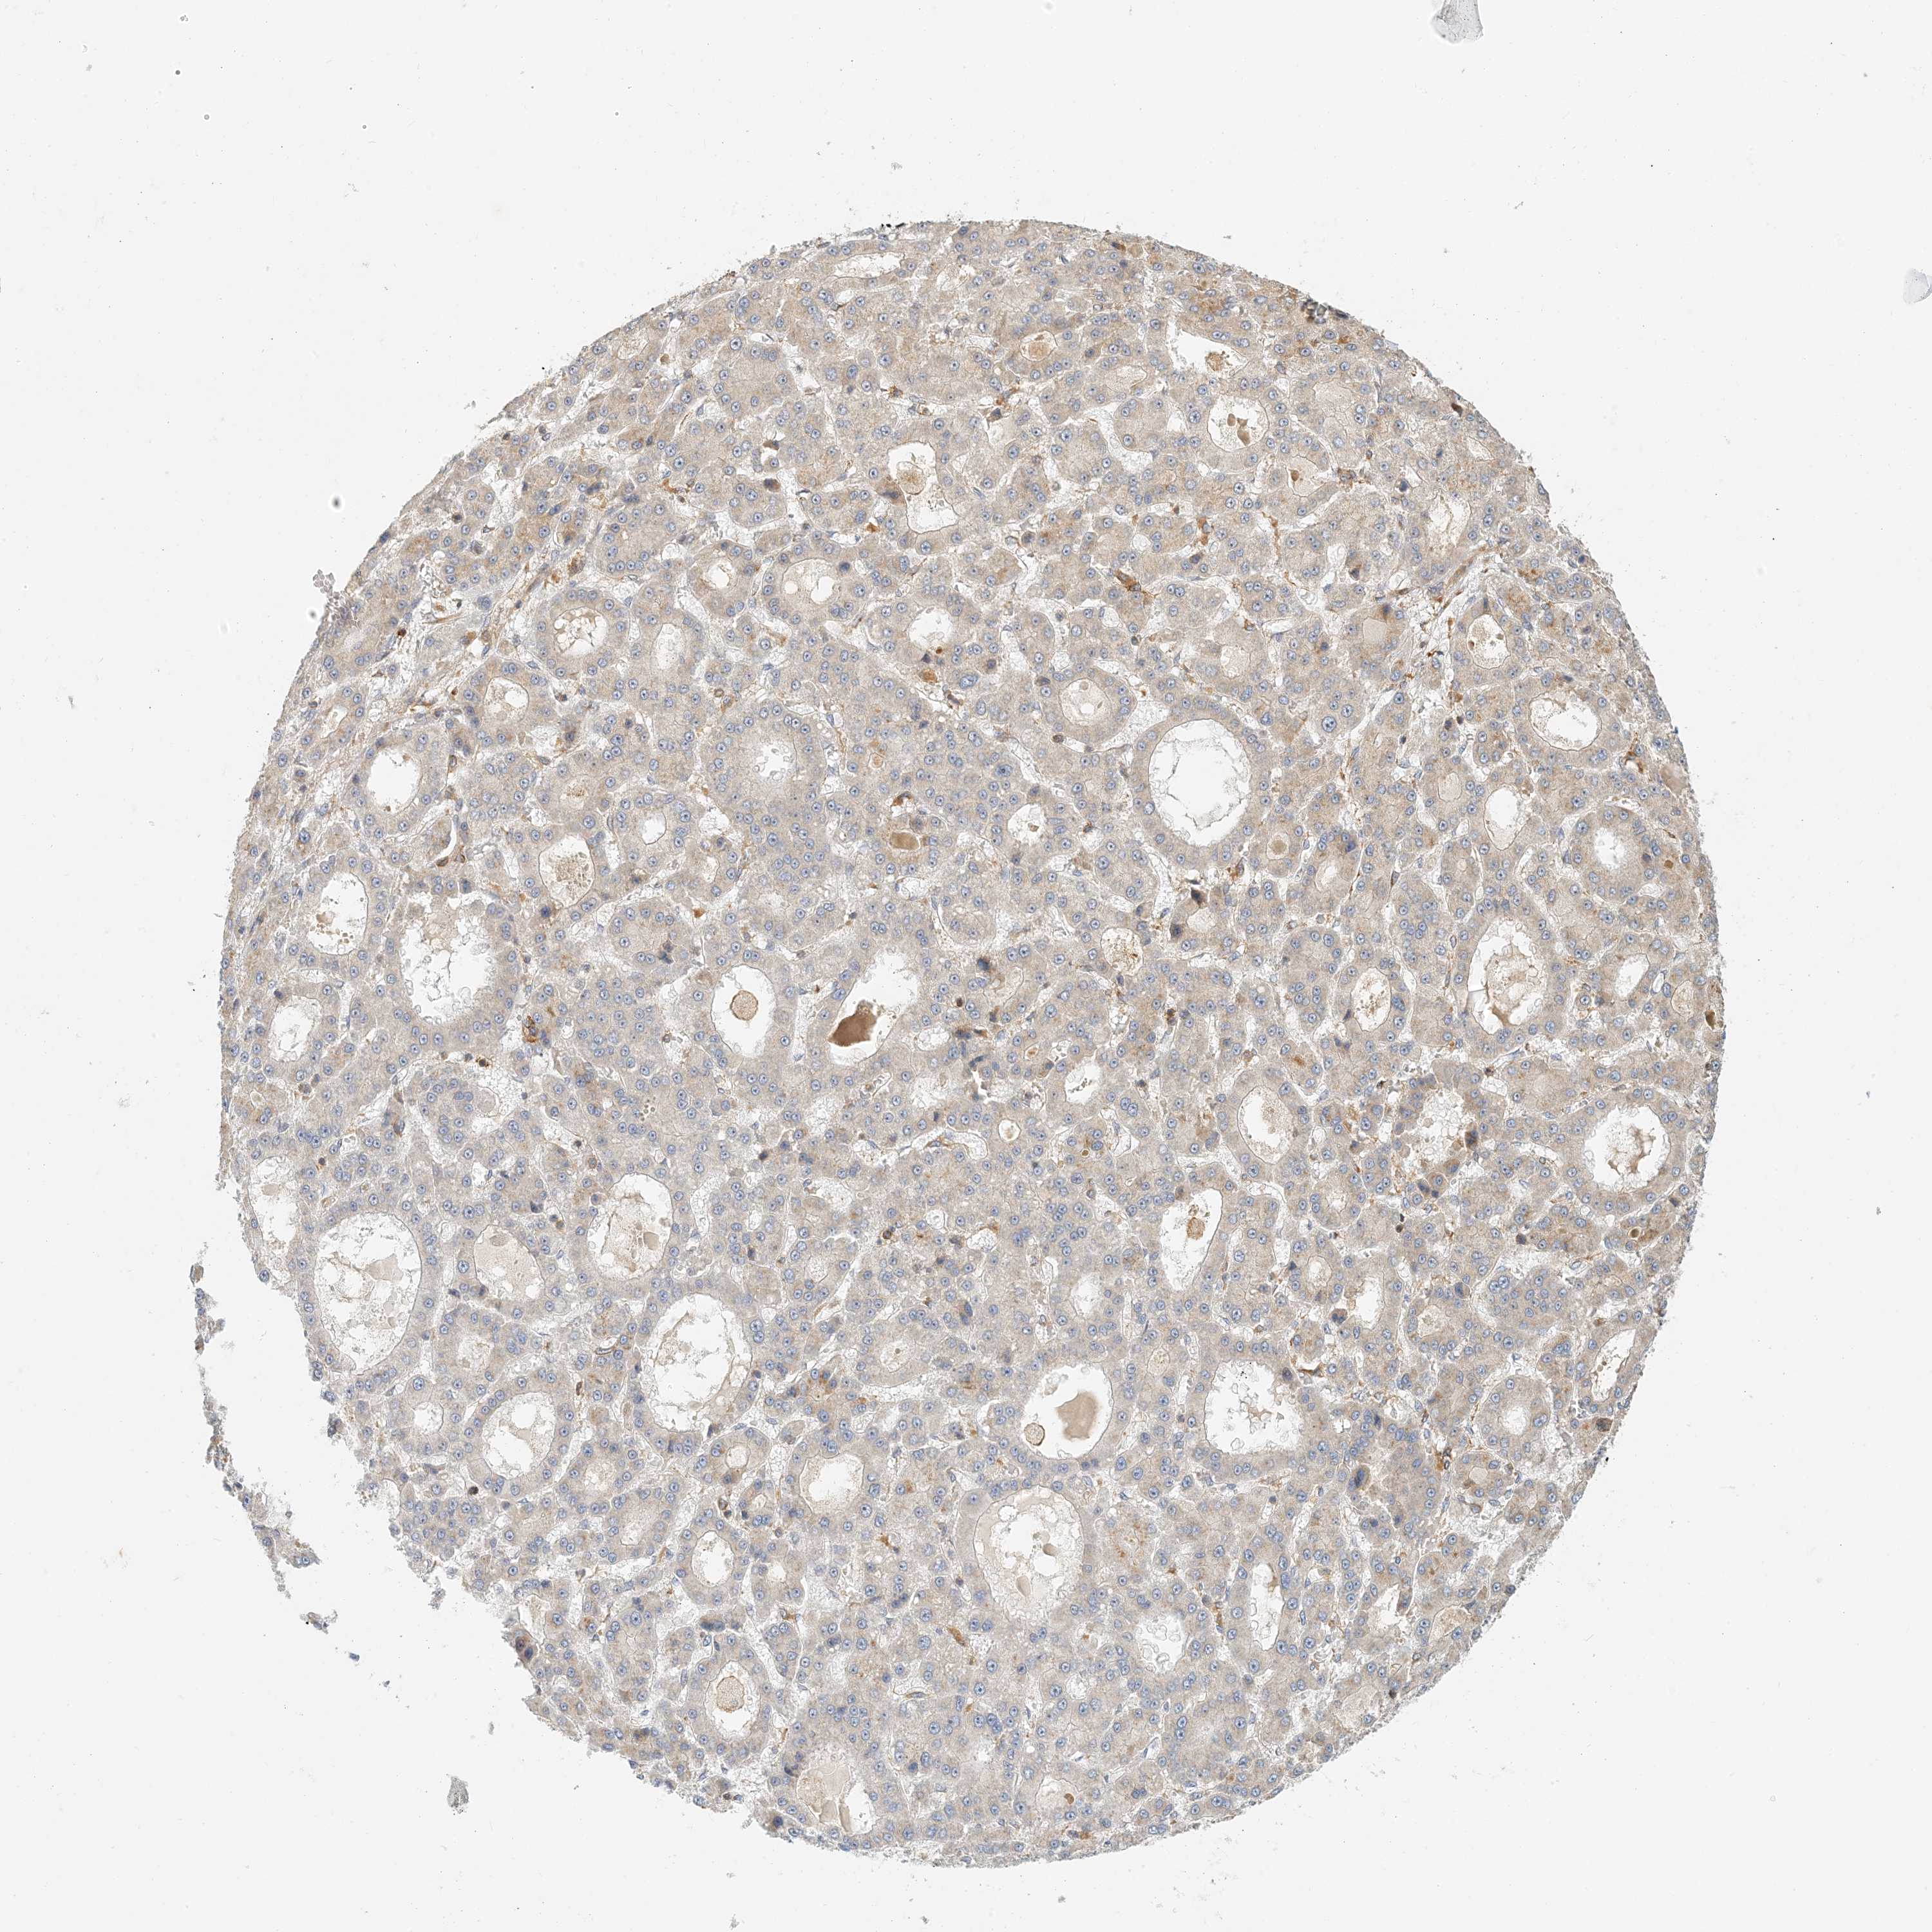

LIVER CANCER - Protein expressioni

A mouse-over function shows sample information and annotation data. Click on an image to view it in a full screen mode. Samples can be filtered based on level of antibody staining by selecting one or several of the following categories: high, medium, low and not detected. The assay and annotation is described here.

Note that samples used for immunohistochemistry by the Human Protein Atlas do not correspond to samples in the TCGA dataset.

Antibody stainingi

Antibody staining in the annotated cell types in the current human tissue is reported as not detected, low, medium, or high, based on conventional immunohistochemistry profiling in selected tissues. This score is based on the combination of the staining intensity and fraction of stained cells.

Each image is clickable and will lead to virtual microscopy that enables deeper exploration of all samples and also displays staining intensity scores, fraction scores and subcellular localization as well as patient and tissue information for each sample.

Antibody HPA035241

Staining

High

Medium

Low

Not detected

Intensity

Strong

Moderate

Weak

Negative

Quantity

>75%

75%-25%

<25%

None

Location

Nuclear

Cytoplasmic/membranous

Cytoplasmic/membranous,nuclear

Cholangiocarcinoma

Carcinoma, Hepatocellular, NOS